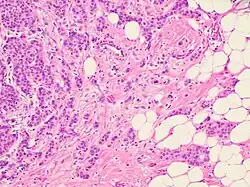

Histopathologic criteria

On microscopic evaluation carcinomatous cells are seen below the basement membrane of lactiferous ducts and invade into the surrounding breast stroma. Otherwise, there are no specific histologic characteristics, essentially making it a diagnosis of exclusion.[21] The histopathologic characteristics seen in these lesions are heterogenous. The cells of a lesion of invasive carcinoma NST may retain >70% ductal differentiation or appear completely undifferentiated. The tumor cells may be arranged in sheets, nests, cords, or singly distributed. They are pleomorphic (i.e., vary in size and shape). They usually have prominent nucleoli and multiple mitotic cells per magnified field of view, which are features generally consistent with cancerous cells. The surrounding non-ductal tissue, known as stroma, can range from none to abundant.[22][23]

Small inclusions of special features may be present within an invasive carcinoma NST tissue sample, but will be 'limited' (i.e. <10%). Carcinomas of mixed type will have a specialized pattern or lobular carcinoma in the majority (i.e. at least 50%) of the tumor and a non-specialized pattern in between 10 and 49% of the sample. Thus, such tumors will be called mixed invasive NST and special type or mixed invasive carcinoma NST and lobular carcinoma.[24]

Invasive ductal carcinoma of the breast. H&E stain.